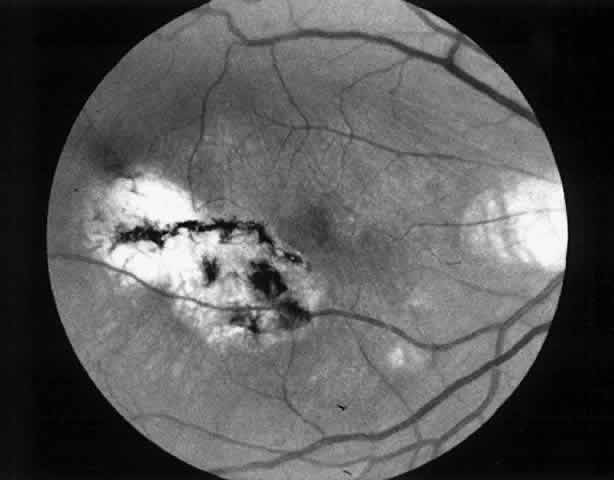

1. A 35-year-old patient with serpiginous choroidopathy developed a recurrent choroidal neovascular membrane extending into the fovea with a decrease in vision to 20/200 (6/60) (Fig. 7). Five months after surgery his visual acuity had improved to 20/25 (6/7.5) (Fig. 8).

Fig. 8. Postoperative fundus photograph (case 1). Five months after surgery, patient's visual acuity is 20/25 (6/7.5).